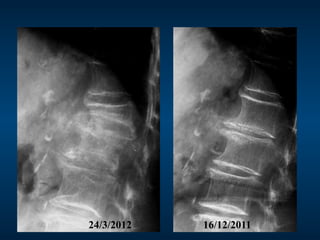

Radiograph (X-ray)

24/3/2012

24/3/2012 16/12/2011

•  85 year old female

•  Severe acute on chronic mechanical

back pain

– Can’t sleep

– Limited walking to only a few steps

•  Spontaneous onset

•  No known trauma